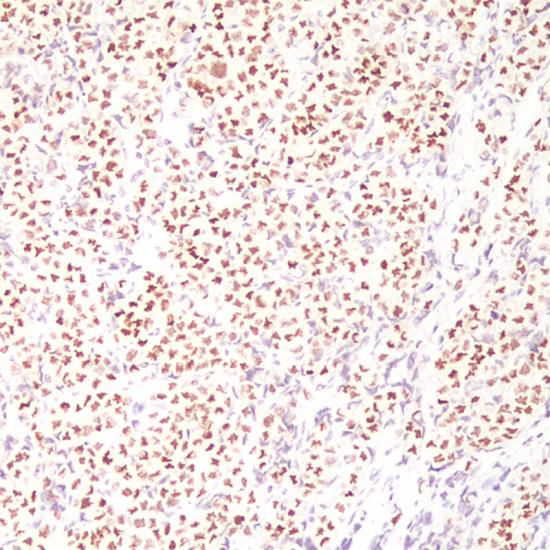

GATA-3

GATA3抗體試劑(免疫組織化學(xué)) 閩廈械備20180095號(hào)

細(xì)胞核

乳腺癌

GATA3是一種鋅轉(zhuǎn)錄因子,在許多組織和細(xì)胞類(lèi)型中對(duì)促進(jìn)和引導(dǎo)細(xì)胞增殖、發(fā)育和分化起到重要作用。在乳腺癌和尿路上皮癌高度特異表達(dá)。GATA3表達(dá)于乳腺小葉癌和浸潤(rùn)性導(dǎo)管癌,同時(shí)在乳腺癌中GATA3表達(dá)與ER、PR成正相關(guān)系,與HER-2成負(fù)相關(guān)系。